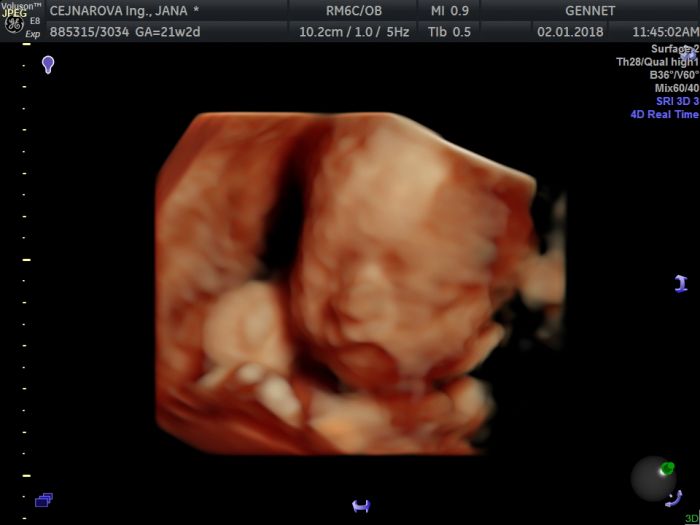

Ahojky holky, s tím dr mě teda překvapujete. Tak to abych tam pak tady teda zavolala dříve. Mám vybraného pediatra v malém městečku, tak snad nás vezme. Je to od domu 5 km, nehodlám jezdit nějak daleko. Jinak jsme byli na screeningu, Eliška potvrzena a vše je v pořádku

. Přikládám naše prtě, co myslíte, mám se objednávat na 4d ultrazvuk, když mi zadáče udělal 3d fotku? Zas za pár týdnů by to mohlo být vidět lépe i s nahrávkou, ale jestli to nebude 800 Kč v tahu.